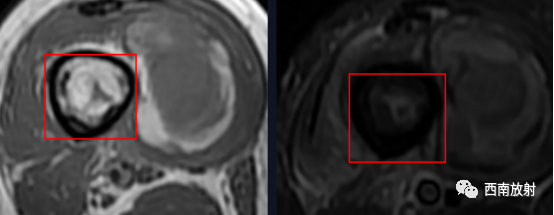

关于脂肪征

▲MRI脂肪征:病灶内单发或多发,T1WI上呈高信号,脂肪抑制序列信号明显减低。急性骨髓炎的脂肪球征发生机制:骨髓炎的炎性反应致骨髓腔内充血、渗出及水肿最终导致髓内压力增高,髓腔内大量脂肪细胞(即髓脂细胞)快速坏死释放出游离脂质并聚集形成脂肪球[2-3]。